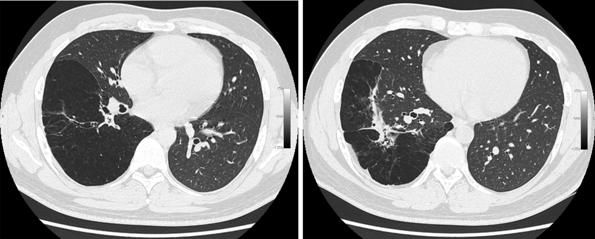

A 35-year-old male was admitted to our department for surgery having been diagnosed with CCAM and bronchial atresia. A CT scan showed a cystic lesion in the right lower lobe according to CCAM (Figure 1). Bronchoscopy revealed absence of segment 6 bronchus. He had been suffering from recurrent pneumonias since childhood. Due to persistent symptoms he was offered lung resection by video-assisted thoracoscopic surgery (VATS). The entire lower lobe was transformed into a huge cyst, so a right lower lobectomy was performed through a single 4 cm incision with no rib spreading.

Figure 1. CT scan showing a huge cystic lower lobe.